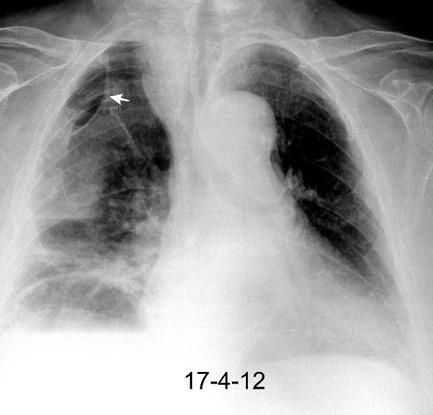

VIH+. 1 mes antes derrame pleural en el curso de una

infección